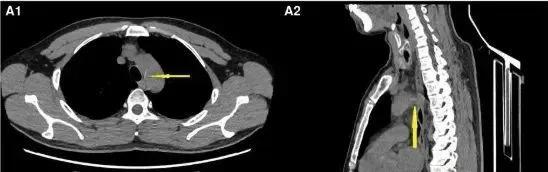

2023 年 4 月亮,病人因误吞鱼刺,自吞馒头后误以为鱼刺已经脱落;2 天后,由于胸骨后不适,就医当地医院,通过胸部 CT 意外发现鱼刺已经通过食道刺入胸部主动脉,形成致命的食道主动脉瘘。

胸部断层 CT 图像:箭头所指的白色条状物是鱼刺

那天晚上紧急开胸手术没有发现鱼刺,术后复查显示鱼刺移动到腹腔动脉,于是转诊到华西医院。5 天后,华西治疗期间突然腹痛。经过多学科会诊,鱼刺最终被锁定并游走至肝动脉。第二次开腹手术后,成功取出。 2cm 修复血管的鱼刺。